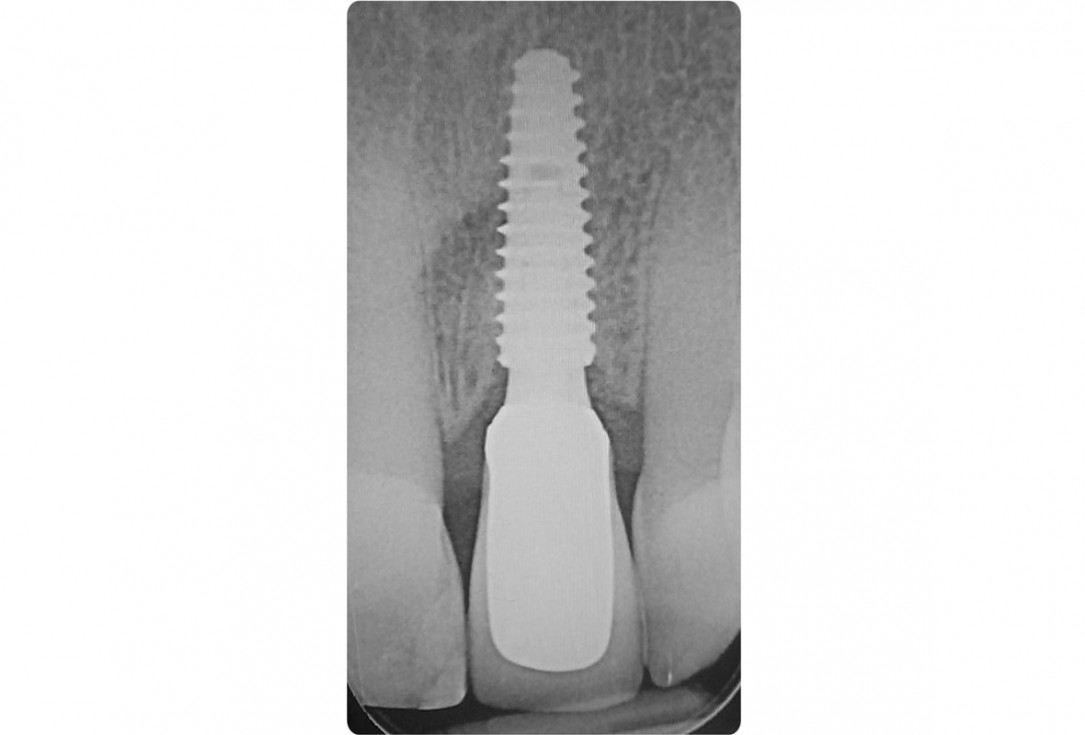

18/18 - X-ray with final prosthetic restorationTooth extraction and socket sealing with mucoderm® - Dr. A. Rossi